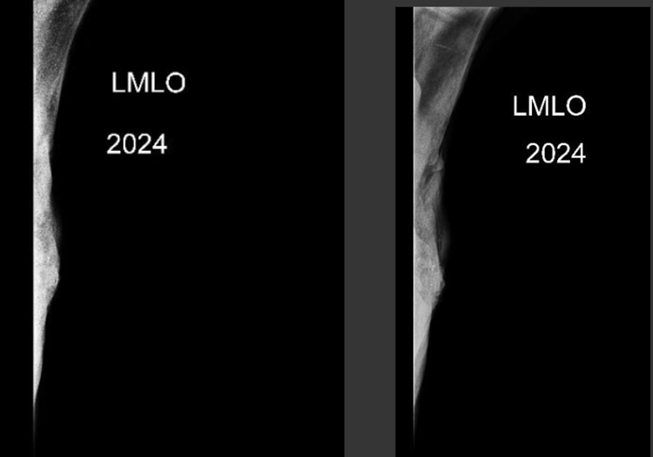

Imágenes Mx

Informe Mamografía

Antecedentes de una neoplasia mamaria izquierda conocida no tratada.

Hallazgos:

No es posible obtener imagen de la mama izquierda por una gran lesión palpable retraída con compromiso de piel asociado.

Mama derecha muy densa con un área de aspecto pseudonodular en su aspecto más posterior mal delimitado que se correlaciona con lesión sólida en ultrasonido.

Conclusión:

Antecedentes de neoplasia mamaria izquierda ya conocida sin poder obtener imagen de dicha alteración.

Imagen nodular en la mama derecha de aspecto neoplásico al ultrasonido.

Birads 6.

ACR C.